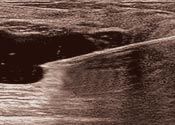

触診だけでは、トラブルの真の姿を捉えることはできません。そのため、当院では最新のデジタル技術を搭載した乳腺用エコーを全院に導入。正確な症状の診断を基に手術を行っています。

- 最新デジタルエコーを導入

- 正確な診断に基づく手術

- 乳腺専門医のWチェックも